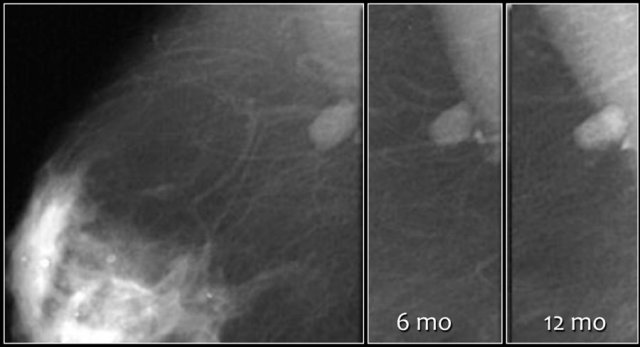

Here a non-palpable sharply defined mass with a group of punctate calcifications.

The mass was categorized as BI-RADS 3.

Continue with follow up images.

Final assessment was changed to a Category 2 Final assessment was changed to a Category 2

• The initial short-term follow-up of a BI-RADS 3 lesion is a unilateral mammogram at 6 months, then a bilateral follow-up examination at 12 months. Assuming stability perform a follow-up after one year and optionally after another year.

• If the findings shows no change in the follow up the final assessment is changed to BI-RADS 2 (benign) and no further follow up is needed.

Follow-up at 6, 12 and 24 months showed no change and the final assessment was changed into a Category 2.

Nevertheless the patient and the clinician preferred removal, because the radiologist was not able to present a clear differential diagnosis.

So add the following sentence in your report:

• BI-RADS 2 (benign finding).

• Instead of stopping the follow-up, tissue diagnosis will be performed, due to patient and referring clinician concern.

PA: benign vascular malformation.

The upper image shows a few amorphous calcifications initially classified as BI-RADS 3.

At 12 month follow up more than five calcifications were noted in a group.

The findings were now classified as BI-RADS 4.

This proved to be DCIS with invasive carcinoma.